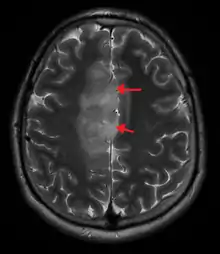

An X-ray computed tomography (CT) or magnetic resonance imaging (MRI) scan is necessary to characterize the anatomy of this tumor as to size, location, and its heter/homogeneity. However, final diagnosis of this tumor, like most tumors, relies on histopathologic examination (biopsy examination).[3]